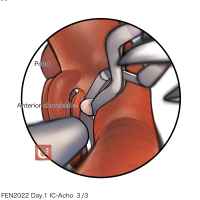

FEN2022シリーズ